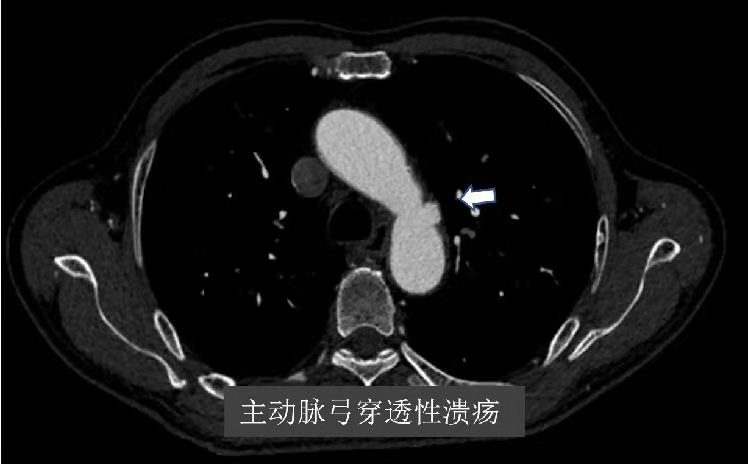

张大爷前不久,因为胸痛至苏州市独墅湖医院(苏州大学附属独墅湖医院)就诊行冠脉疾病治疗,住院期间完善CT血管检查,一查发现他的血管病变不得了。有主动脉弓穿透性溃疡、左侧锁骨下动脉起始段、双侧髂动脉闭塞(左侧重);张大爷诉说自己多年头晕不适、左下肢乏力,去多家医院检查左右上肢血压不一致,相差约40mmhg,左腕部也摸不到血管跳动。但自己一直没有重视,并且张大爷是个“老烟枪”,每天一包多,有糖尿病及高血压病史多年,没想到自己这么多血管出现了问题。

为此,张大爷找到独墅湖医院介入与血管外科张喜成主任,医生们根据影像,认为主动脉弓部穿透性溃疡最危险,很容易导致夹层或破裂引起生命危险,另外左锁骨下动脉、髂动脉均完全闭塞,这些都给治疗上带来挑战。经研究讨论后医生们决定同期解决多处血管问题。手术在我院先进的复合手术室进行,张主任、黄献琛博士和顾铖涛医师密切配合,术中因锁骨下动脉闭塞段的钙化很严重,很难开通,但他们艺高胆大,采用双向穿刺技术成功开通血管,然后用覆膜支架覆盖主动脉的溃疡,但由于溃疡距离左锁骨下动脉较近,故他们采用“浮潜”技术,既盖住了溃疡又保证分支血管的畅通。最后他们又成功开通了闭塞的左髂动脉,并植入血管支架解除了狭窄。